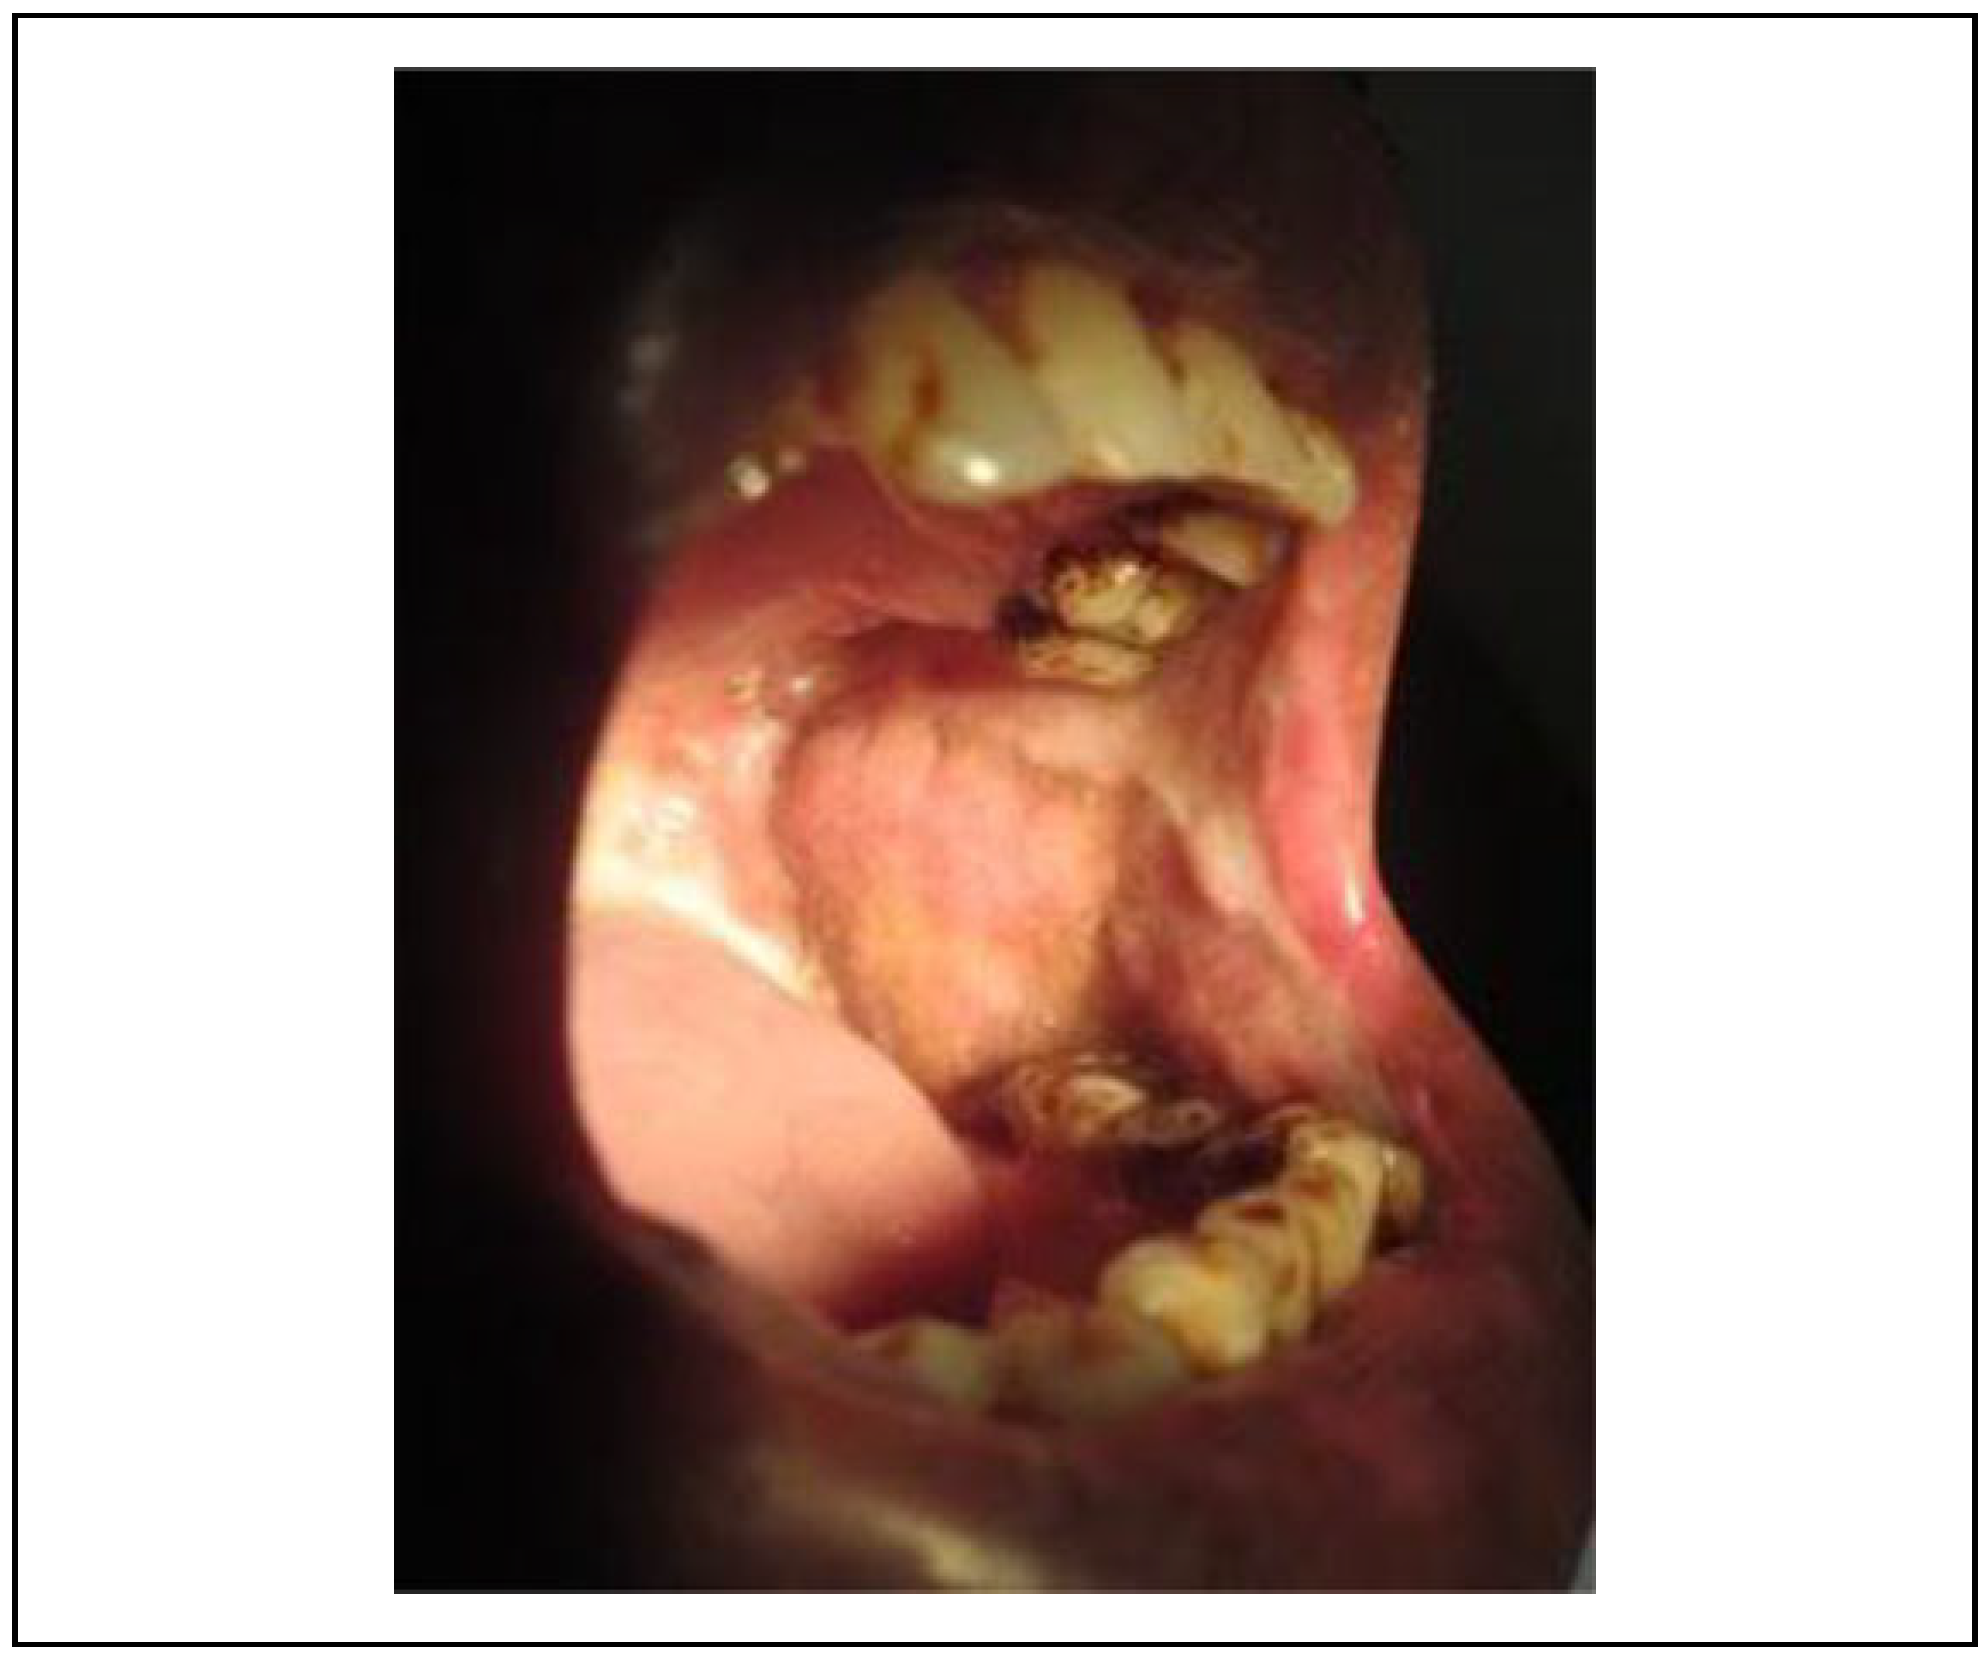

Numerous studies have reported the use of the NLF for the closure of fibrotomy defect and the defects of the upper lip, tongue, and gingival sulcus. The versatility of this flap is attributed to its reliable vascularity derived from numerous vessels in the vicinity. It is advocated because of the ease of elevation, proximity to the defect, minimal swallowing and speech difficulties, and a relatively cosmetic result as the scar is formed in a natural crease. The BFP which has also been used for the coverage of the defect after fibrotic band excision is simple due to easy access[9]; however, the tissue of this flap may be inadequate for the complete coverage of the defect which is the biggest disadvantage of this flap (Figure 3). The gradual recurrence of trismus was observed due to islands of mild secondary fibrosis if aggressive physiotherapy is not performed (Figure 4).

Other studies have reported the following drawbacks of the NLF: extraoral scars and hair growth in male patients. So, in this study, we assessed extraoral scar formation and the patient’s perception. The assessment revealed a satisfactory outcome after 1-year follow-up, even though the temporary widening of oral commissure was observed. It is prudent to counsel the patient going in for NLF about the extraoral scar and weighing the benefits on a long-term basis. In our study, all patients accepted the scar without any significant complaints. The hair growth, although seen in the early postoperative period, was reduced during the follow-up period of 1 year. In NLF group, there was good coverage of raw area following fibrotomy in the early phase of post-surgery and at 1-year follow-up there was appreciable margin adaptation with no evidence of contracture with smooth pliable soft tissue in the reconstructed area. Whereas in BFP group, there was deficient coverage (25%-30%) of raw area and at 1-year follow-up there was evidence of contracture and secondary fibrosis on palpation.

Figure 4. BFP healing with mild secondary islands of fibrosis. BFP indicates buccal fat pad.